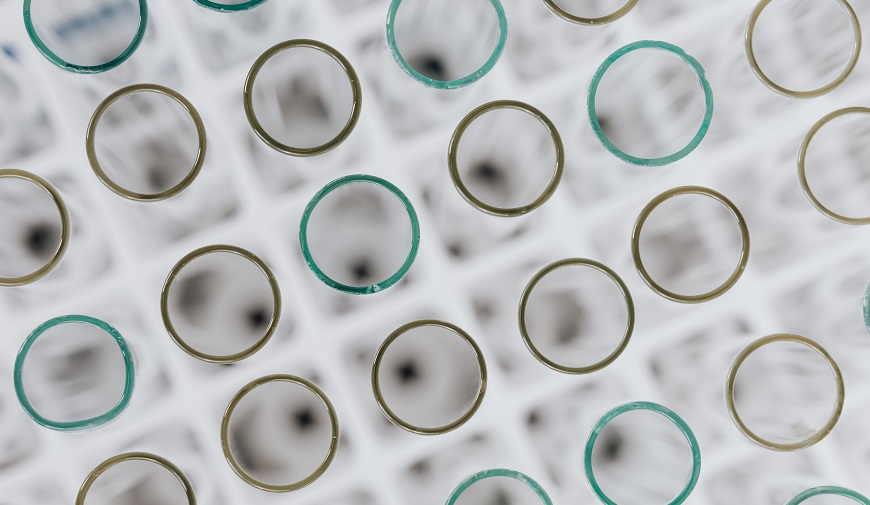

Del mismo modo, la determinación de biomarcadores del dolor, como herramienta complementaria a las escalas observacionales, puede emplearse con el objetivo de diagnosticar, prevenir y evaluar la existencia/presencia de dolor. Esta determinación puede efectuarse en diversos fluidos como el líquido cefalorraquídeo, sangre y saliva, aunque la recolección de esta última es mínimamente invasiva para el paciente y accesible, parámetros fundamentales en cuanto a la consideración del bienestar del paciente. Por otro lado, el concepto de biomarcador supone que cumpla criterios tales como que su determinación debe ser reproducible, segura y costo-efectiva. En este sentido, diversos biomarcadores del dolor presentes en sangre pueden ser también determinados en saliva, como el cortisol salival, la testosterona, la α-amilasa salival, la inmunoglobulina A secretora (sIgA) y el receptor II del factor α de necrosis tumoral soluble (sTNF-RII). De entre todos ellos, estudios recientes han demostrado que sIgA y sTNF-RII son los de mejor reproducibilidad en sujetos sanos.

En este contexto, los resultados de nuestro estudio informan que esto es así, también, en evaluación del dolor en personas con deterioro cognitivo severo. No obstante, es el sTNF-RII el biomarcador que mejor predice el dolor en personas con demencia avanzada e incapacidad de comunicación.

Además, estos resultados indican una alta correlación del sTNF-RII y sIgA con la escala Painad, por lo que ambas evaluaciones pueden ser consideradas como suplementarias, seguras y útiles.

Pero, incluso podríamos decir que los resultados del estudio autorizan/ defienden una posibilidad: la de usar la escala Painad como única estrategia para evaluar el dolor y, de esta forma, minimizar el infradiagnostico del dolor en personas con demencia avanzada.